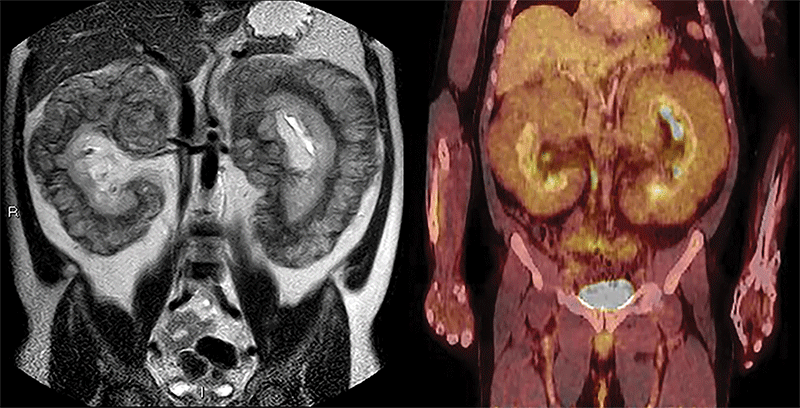

Images in a 47-year-old man with worsening lower extremity edema and chronic abdominal distention. Left: Coronal single-shot T2-weighted MRI scan shows massive bilateral perirenal infiltration by soft-tissue masses. Right: Fluorine 18 fluorodeoxyglucose PET/CT scan shows mild uptake by perirenal masses and upward displacement of liver. https://doi.org/10.1148/radiol.229031 ©RSNA 2022

The other second runner-up tie article is, “Massive Perirenal Involvement in Erdheim-Chester Disease,” by Jorge Polo-Sabau and Begoña López-Botet-Zulueta. The article includes an example of imaging of a rare disease. It serves as a reminder that even in the absence radiologic signs that reflect the most frequent appearances of certain disease conditions, radiologists may still consider certain diagnoses when a combination of imaging details and clinical presentation warrant it.